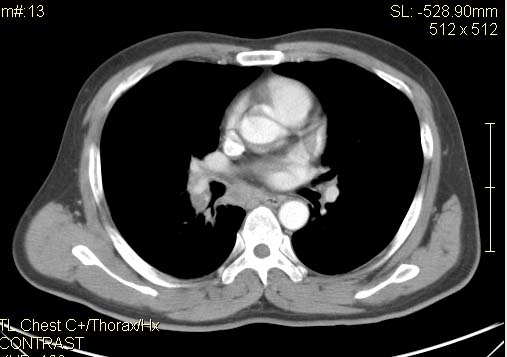

以下是引用qc80012345在2007-4-17 12:33:00的发言:[br]右肺下叶周围型肺癌伴肺门及纵隔内淋巴结转移;比较清楚。

以下是引用qingyuan在2007-4-17 14:19:00的发言:[br]右肺下叶外侧后段胸膜下区节结样病变、分叶、内可见空洞,壁厚薄不均,胸膜凹陷、肺门周围区纹理增粗、僵硬、并近似小结节样改变,肺门区软组织节结、纵膈淋巴结肿大,患者病史长、抗炎治疗无好转炎性改变基本排除,考虑:右肺下叶周围型肺癌伴纵膈及右肺门区淋巴结转移、肺内淋巴管受侵。